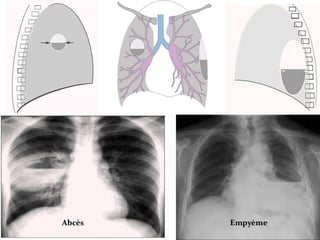

2.IMAGES CAVITAIRES

 Caververne tuberculeuse.

 Abcès.

 Tumeurs excavées.

 Autres causes, mais plus rare.

Images

cavitaires

Abcès

Déclive

Contours flou

Cavité ronde ou

ovalaire

Niveau hydro-

aérique (NHA)

de diamètre

identique F et P

Cavernes tuberculeuse

Apex

Plus anfractueux

Bronche de drainage

Pas de NHA

Micro-nodules

périphériques de Face

de Profil

Abcès Empyème